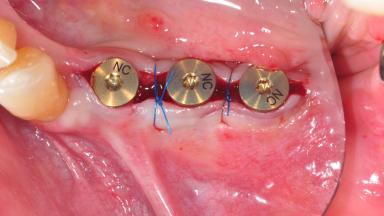

After the placement of three diameter-reduced two-piece implants the bone is augmented with autologous bone chips and DBBM particles to enlarge the crest volume. The surgery is completed with the application of two membrane layers and primary wound closure.

For soft tissue management, the initial healing caps are replaced with a longer type 8 weeks after implant placement in a second intervention before prosthodontic treatment is initiated.

Bone Augmentation Horizontal|Simultaneous

Augmentation Materials Autogenous chips|Xenogenous|Membrane